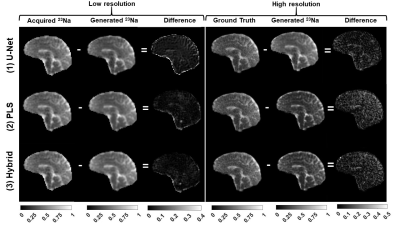

Figure 1: U-Net super-resolution architecture. The asymmetry of the contracting and expanding path makes the output double the size of the input. The convolution layers learn the features in order to produce the finer details in the output.